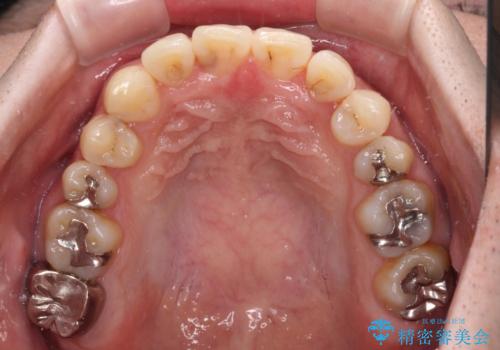

- デコボコした前歯をセラミックできれいに揃えたいとのことで来院された患者様です。

歯を削って整えることは簡単ですが、健全な歯を削って後悔してからでは遅いため、矯正治療を提案しました。

はじめは矯正治療の期間が長いことに悩んでいらっしゃいましたが、ある程度整えば満足するだろうとのことで、インビザラインにて矯正治療を行うこととしました。

左上の犬歯が欠損しているため、正中の位置や奥歯の咬み合わせが理想的にならない点を了承していただきました。